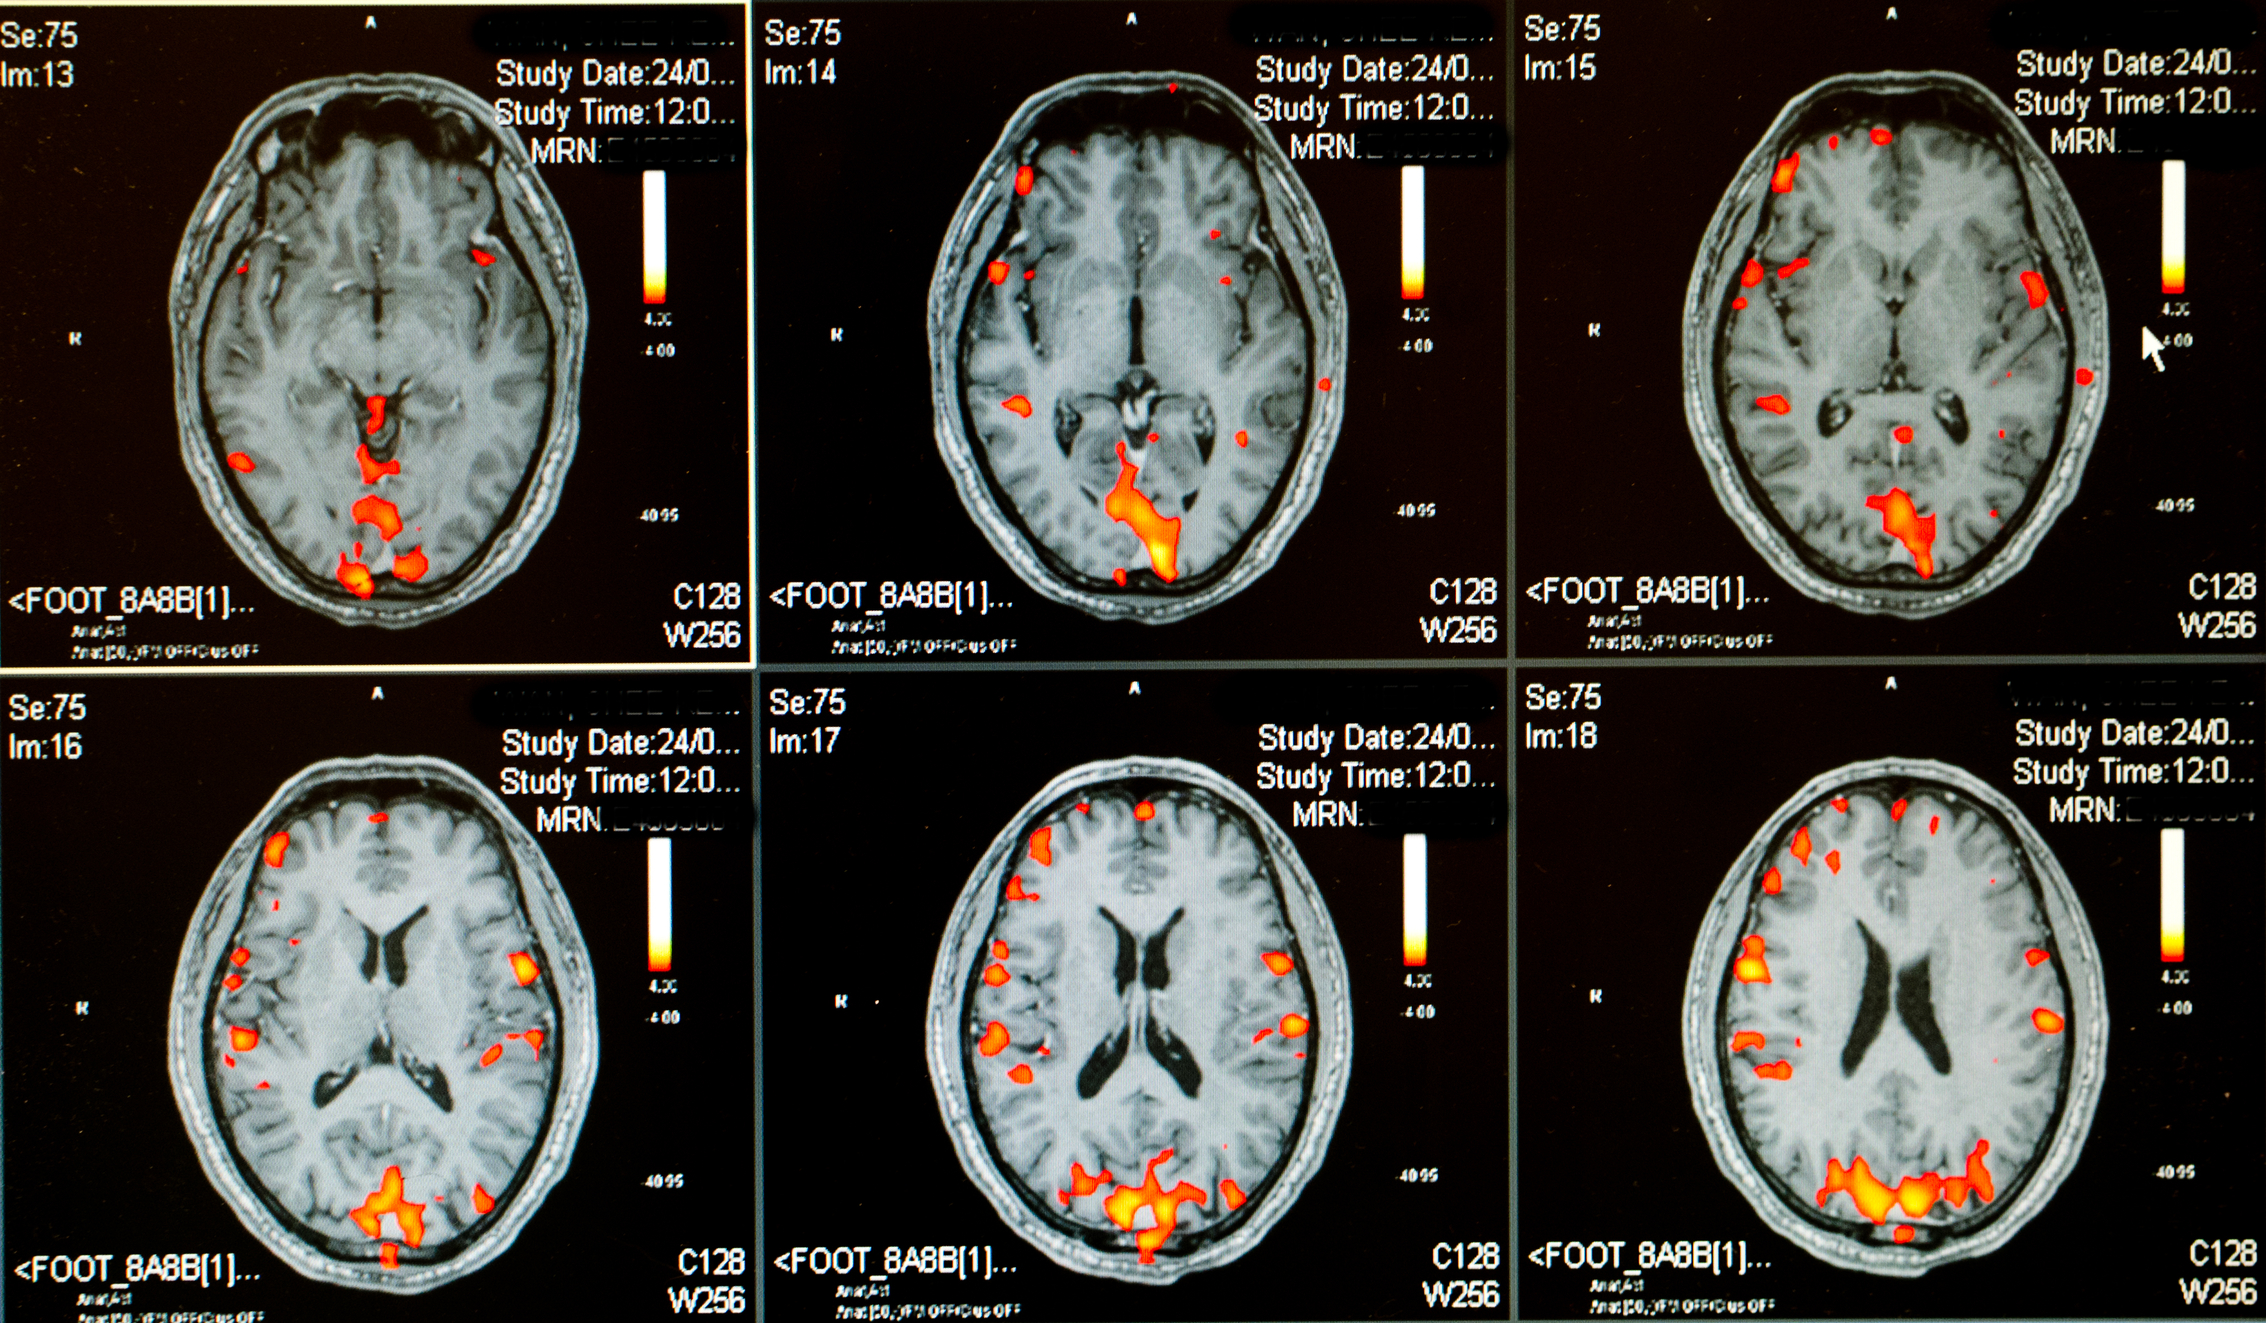

Artificial intelligence (AI) is improving how doctors diagnose neurological disorders with greater accuracy. Machine learning algorithms analyze brain scans, detecting abnormalities that might be missed by human specialists.

NIH notes that AI can now replicate human perception and decision-making, improving accuracy in neural analysis. Neuroscience research increasingly relies on AI to uncover complex brain functions through advanced data-driven insights. Healthcare is evolving into a human-AI collaboration, optimizing patient outcomes.

These tools help doctors recognize early signs of conditions like Alzheimer’s, epilepsy, and multiple sclerosis. AI-powered diagnostics enhance decision-making by providing more precise and reliable assessments of brain activity.

Early detection leads to faster interventions, potentially slowing disease progression and improving patient outcomes. Neurologists now rely on AI for detecting patterns that indicate neurological conditions before symptoms appear.